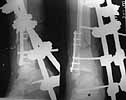

Emergent closed reduction performed, and Tibial wound debrided. Next day Exfix applied and fibula plated. Initially femoral head fracture was not appreciated and it was thought that this is a posterior wall fracture. Presently two weeks down the line, Tibial wound is better but not completely healthy. and plastics want to wait for another five days, before they flap it. I enclose radiographs, Judet view, Ct scans in this and following mails.

Based on the selected images that you shared with us, I would not leave it as is. The fragment is significant in terms of its size and location and displacement.

Standard 3.5 mm screws can be used but they have a more prominent head profile than the smaller screws. Further fragmentation due to the screws will depend more on their location and application than size.